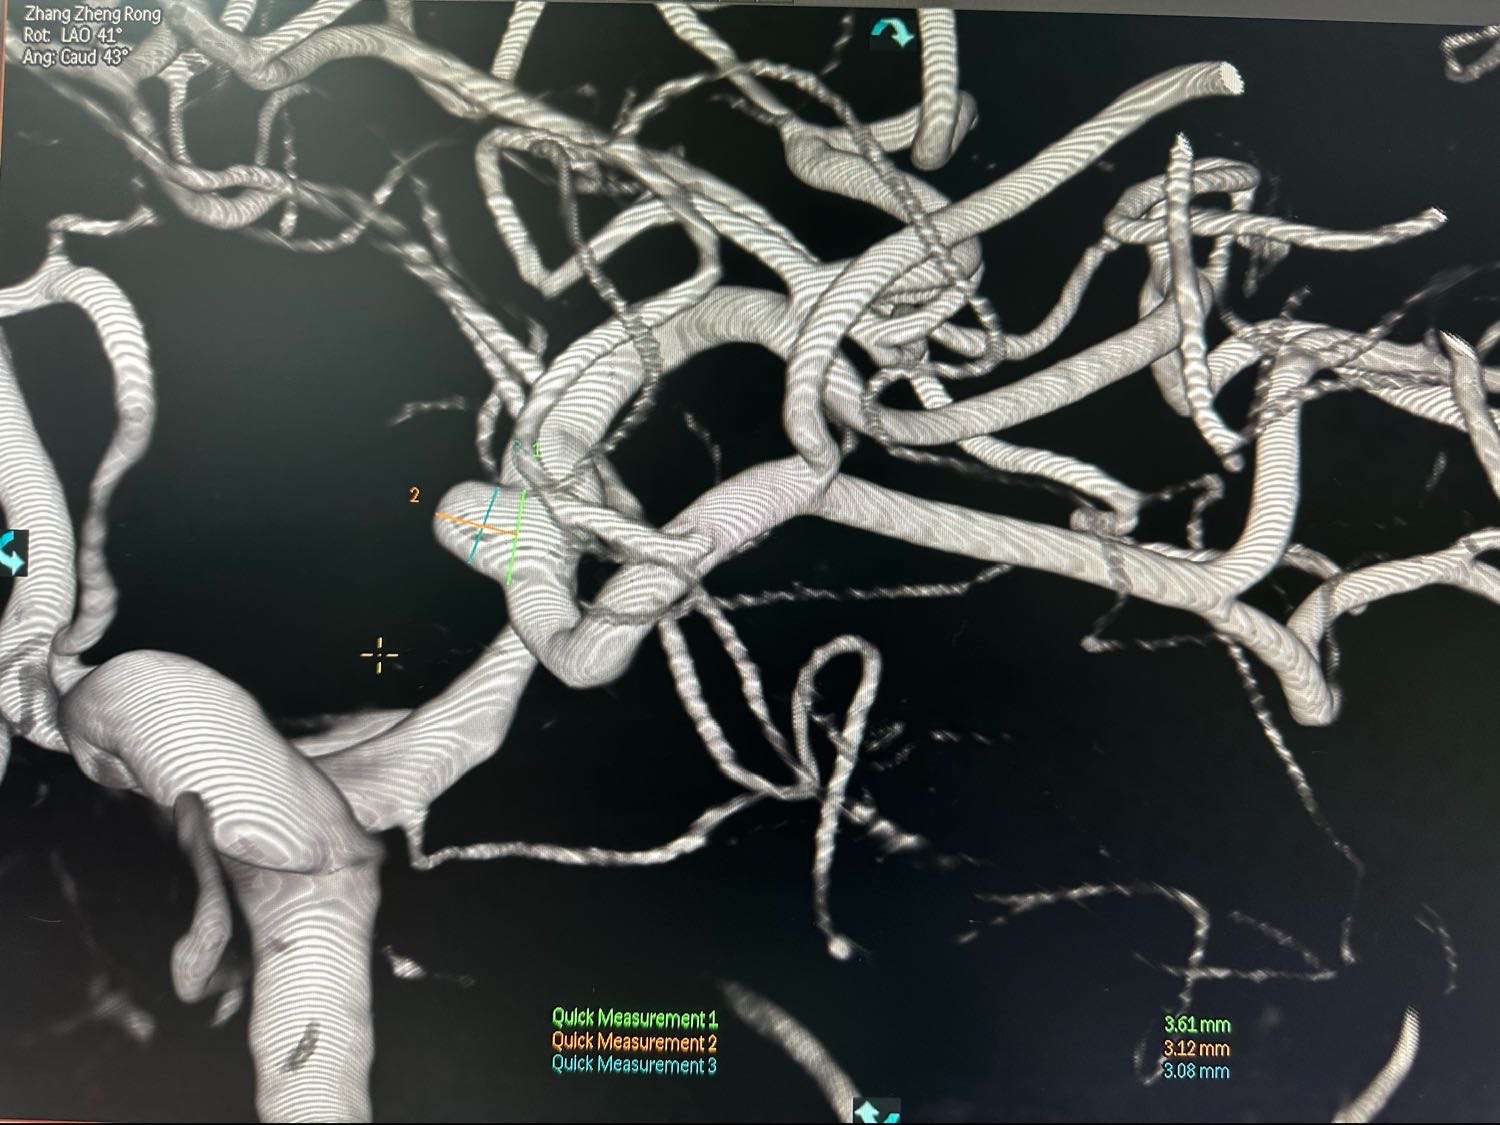

左侧颈内动脉术前3D图像

另外一个角度,动脉瘤大小约3mm左右,宽颈

另外一个角度